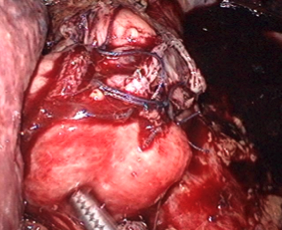

血管の処理が終わるといよいよ胃を全摘出します。そして、持ち上げた小腸と食道をつなぎ合わせます。

つなぎ合わせる手技もお腹の中で行います。

体の深い場所での操作ですが、カメラで拡大されているため周りを確認しながら安全に行うことができます。

つないだり、切り離しの準備のために食道の周りを十分に露出しておきます。

ホチキスを入れるための穴を食道に開けます。同様の穴を小腸にも開けます。これで小腸と食道をつなぐ準備ができました。